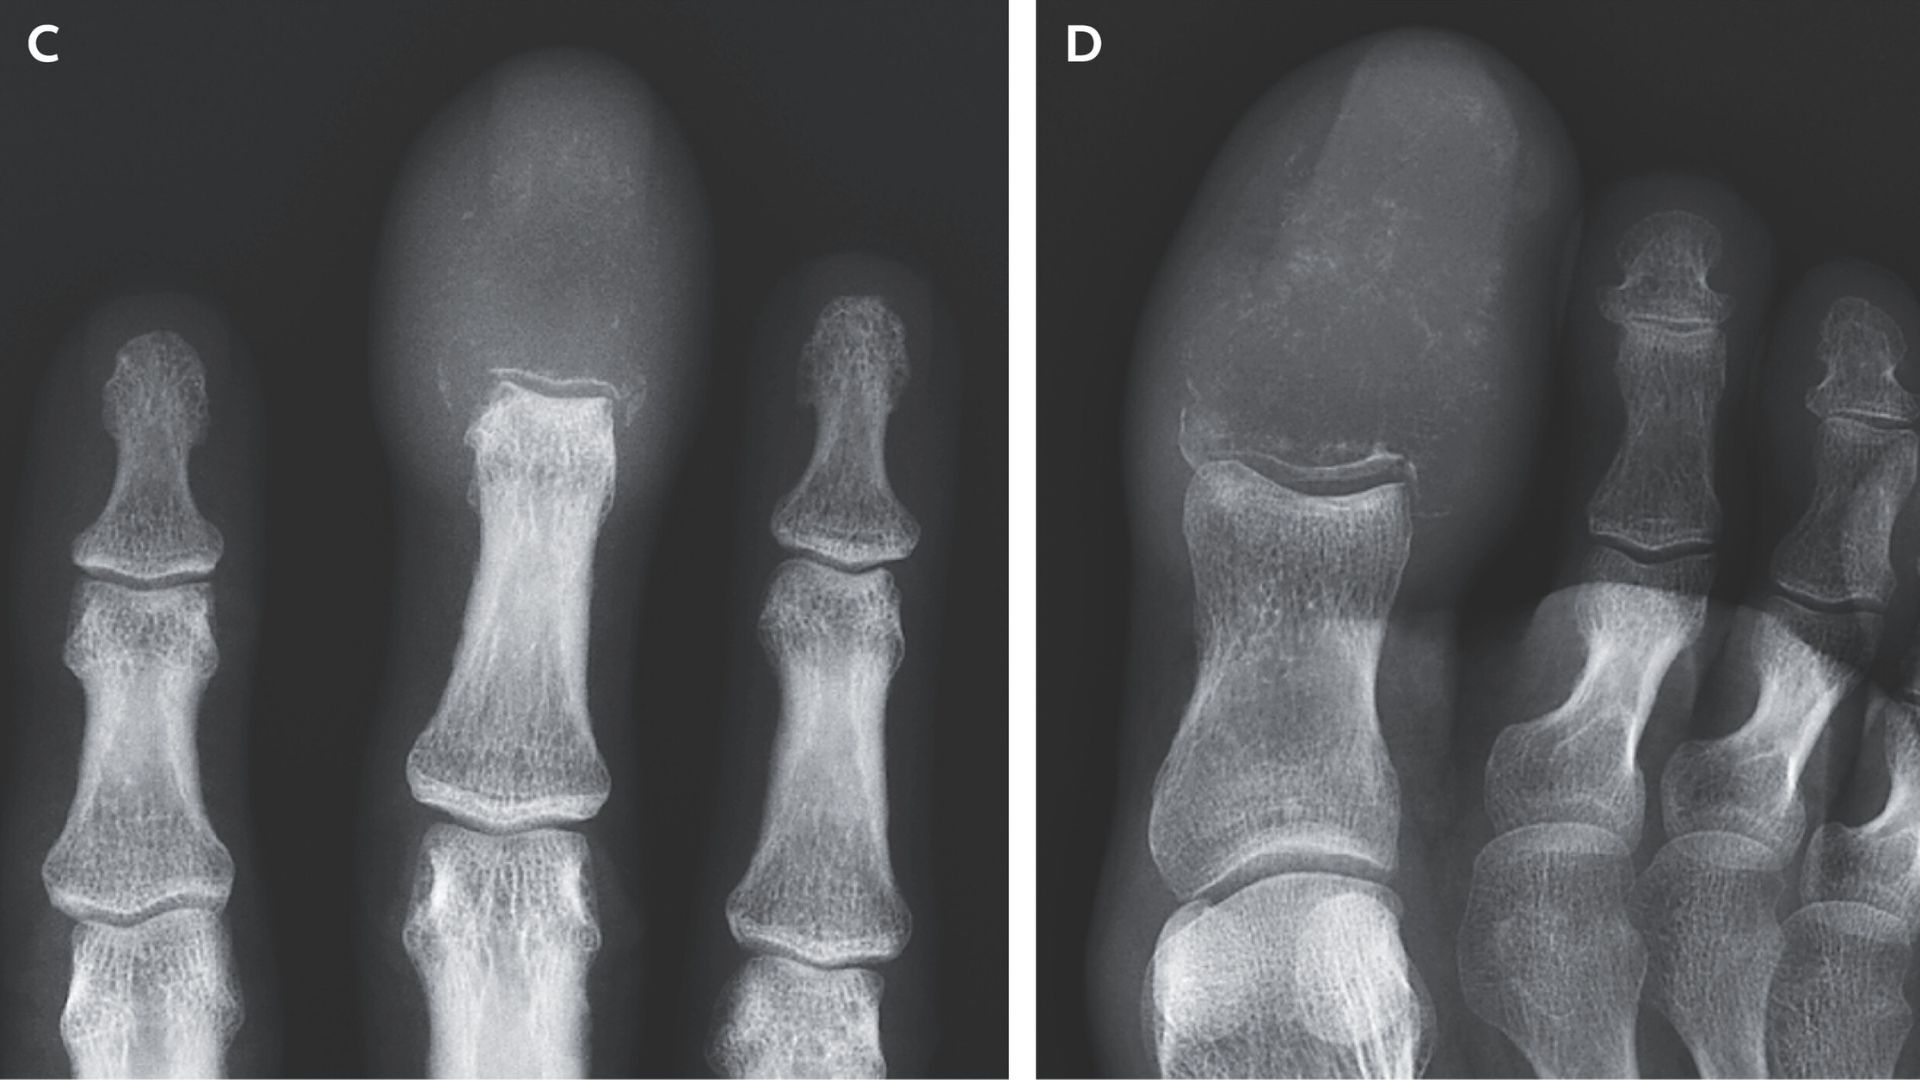

Рентгенографія ураженої ділянки – дозволяє помітити руйнування, дефекти, утворення пухлинної маси.

Комп’ютерна томографія (КТ), магнітно-резонансна томографія (МРТ) – деталізують розміри, глибину, поширення пухлини, дають інформацію про стан м’яких тканин, суглобів, можливі метастази.